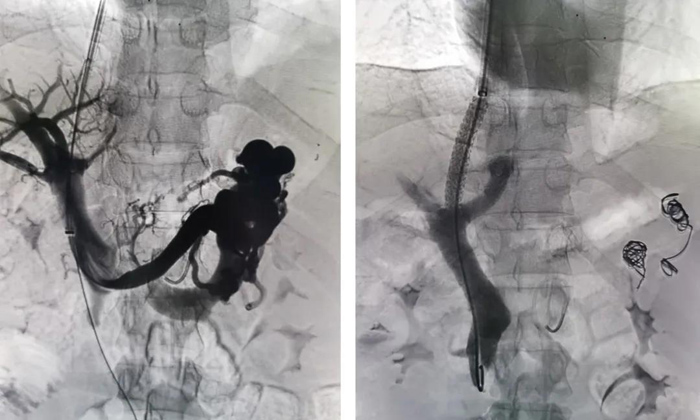

手術(shù)如期進(jìn)行,李強(qiáng)主治醫(yī)師施行此次手術(shù)。術(shù)中由頸靜脈處穿刺插管至肝靜脈,在肝實(shí)質(zhì)內(nèi)穿刺門靜脈,并植入支架,建立門靜脈與肝靜脈之間的通道;手術(shù)同時(shí)栓塞曲張靜脈,從而降低門靜脈壓力,減輕食管胃底靜脈曲張程度及出血風(fēng)險(xiǎn)。最終手術(shù)順利完成,患者和家屬臉上也露出了滿意的微笑。